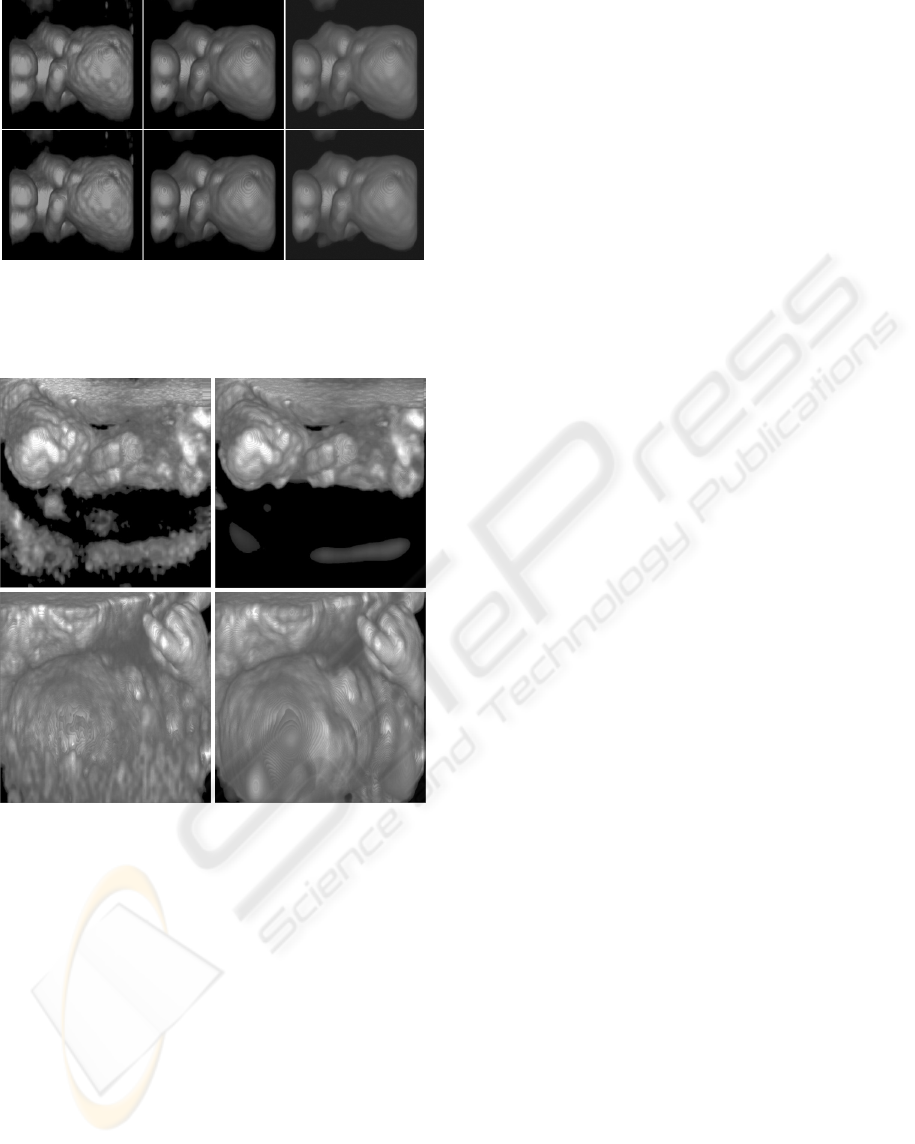

Abstract: Ultrasound imaging is used in a variety of medical areas. Although its image quality is inferior to that of CT

or MR, it is widely used for its high speed and reasonable cost. However, it is difficult to visualize ultra-

sound data because the quality of the data might be degraded due to artifact and speckle noise. Therefore,

ultrasound data usually requires time-consuming filtering before rendering. We present a real-time 3D filter-

ing method for ultrasound datasets. Since we use a CUDA

TM

technology for 3D filtering, we can interac-

tively visualize a dataset. As a result, our approach enables interactive volume rendering for ultrasound

datasets on a consumer-level PC.